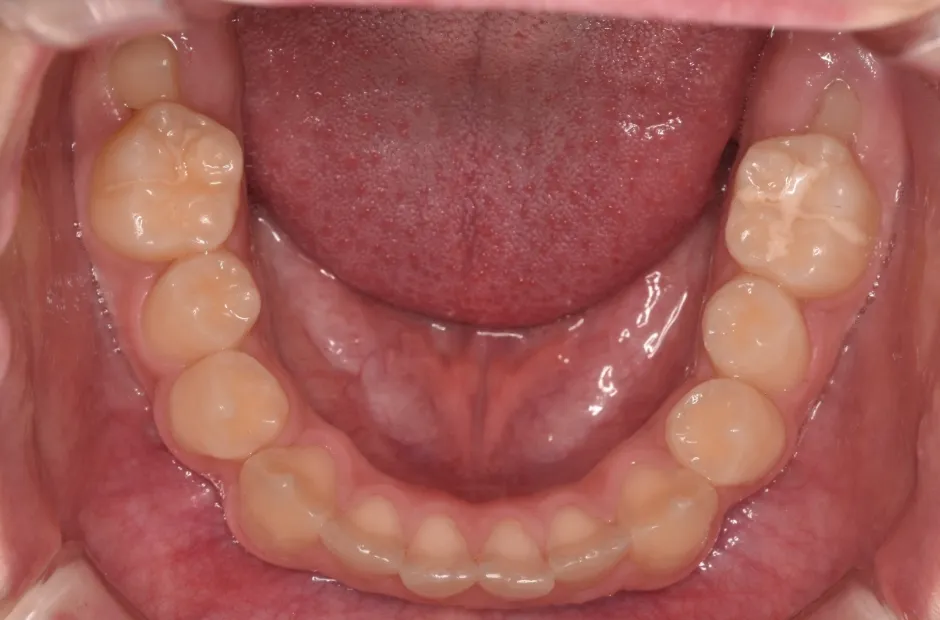

先天欠如

| 診断名・主訴 | 先天欠如 |

|---|---|

| 年齢・性別 | 14歳・女性 |

| 治療期間・回数 | 2年 |

| 治療に用いた主な装置 | ブラケット矯正 |

| 抜歯部位 | なし |

| 治療費 | 60万円(税抜) |

| リスク・副作用 | 装置による違和感・疼痛・歯肉退縮・歯根吸収・虫歯のリスクなど |

治療前